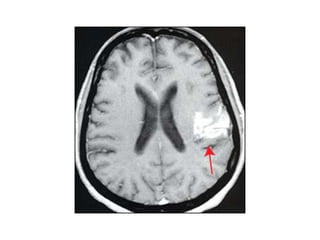

MCA syndrome MCA isthe second of the two main branches of the internal carotid artery. Supplies: • Lateral aspect of cerebral hemisphere( frontal, temporal, and parietal lobes ) • Subcortical structures (IC, corona radiata , globus pallidus, putamen )

Signs and symptoms: • • • • • • Contralateralhemiparesis (UL and face > LL) Contralateral sensory loss (UL and face > LL) Motor speech impairment Receptive speech impairement Global aphasia Perceptual deficits (unilateral neglect, anosognosia, apraxia and spatial disorganization) • Contralateral homonymous hemianopsia • Sensory ataxia Structures involved : Primary motor area, primary sensory area, broca’s area, Wernicke’s area, optic radiation in internal capsule